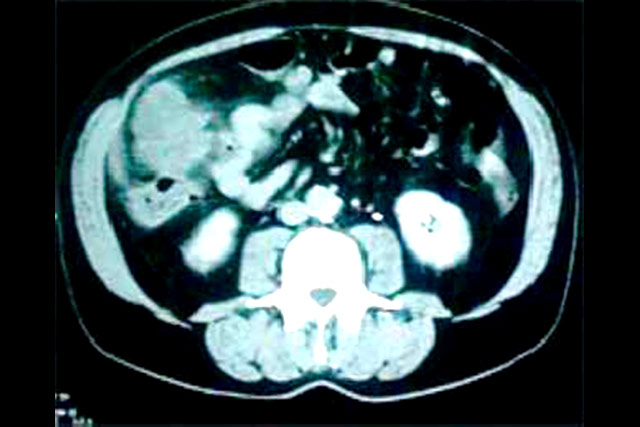

Tomografia de abdome apresentando

tumoração de colon em seu ângulo hepático.